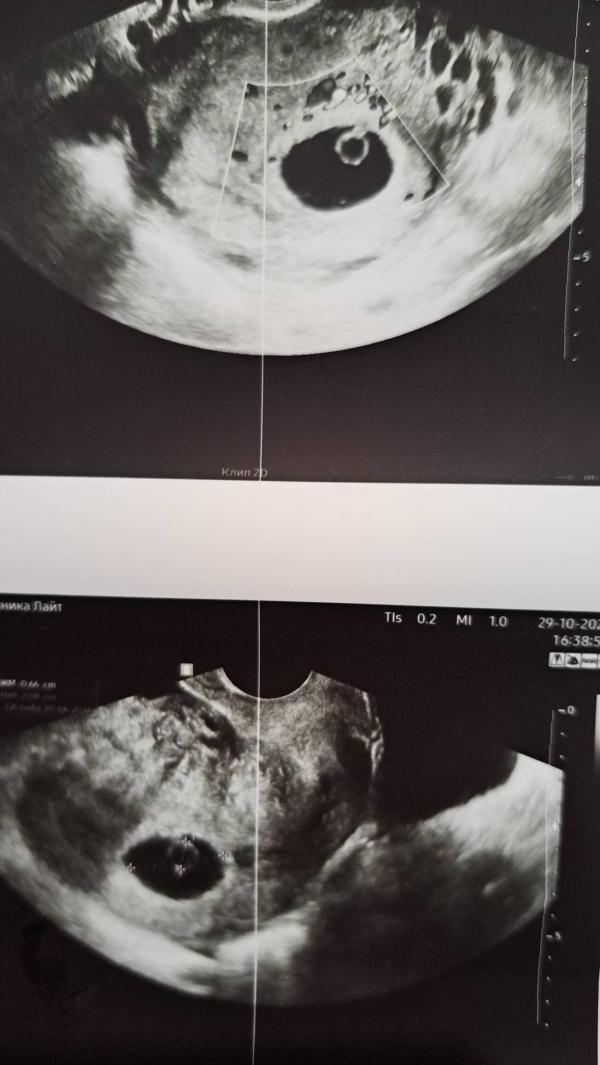

Первые два фото 22.10, последние два фото сегодня. Овуляция 13.09 была, отслежена и подтверждена. По месячным срок 8.5.

А что за точка на верхнем фото с сегодняшнего узи?

@snezhik.mm вот да, но по сроку маловато конечно.

Там и рядом какие-то вкрапления, думаю оттуда и есть. На нижнем скрине же нет ничего